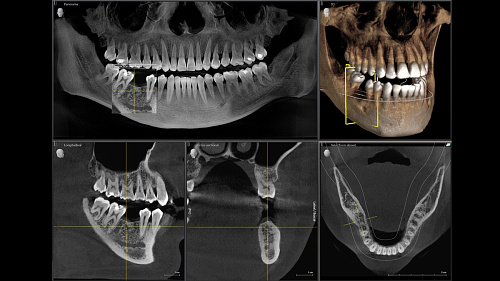

Диагностика последнего поколения, идеально решающая задачи рентгеновского обследования независимо от размеров клиники. Поля изображения зависят от определенной клинической картины, поэтому специалистам так удобно работать с ORTHOPHOS SL 3D. Данная установка делает объёмные картинки для одиночной реставрации в 3D качестве полностью всей челюсти такого размера, которого требуется.

Планирование одиночной реставрации, эндодонтические исследования и пр. – для этого специалист может выбрать объёмные варианты 8 х 8 см или 11 х 10 см, также предлагается объём 5 х 5,5 см. Снимки в HD-качестве, стандартные настройки или выбор объёма обследования в зависимости от диагноза — всё это врач получает в отличном качестве, а для пациента излучение в районе исследования минимально.

С технологией SL можно за один сеанс получить огромное количество снимков. Те из них, где фокусировка наиболее чёткая, автоматически соединяются. В итоге одна процедура — снимки челюсти полностью в самом лучшем качестве. Даже нестандартные случаи не станут помехой в обследовании. К примеру, при ретинированных зубах уже после того, как снимок сделан, нужную область можно выделить подробнее, и в ещё одном рентгене необходимость отпадает.

Программное наполнение для работы с изображениями с модулем MARS*

Металлические элементы в ротовой полости могут привести к возникновению помех на снимке. Благодаря наличию программного обеспечения MARS наличие объектов из металла определяется автоматически, влияние артефактов нивелируется. Таким образом не требуется повторного изображения для уточнения диагноза.